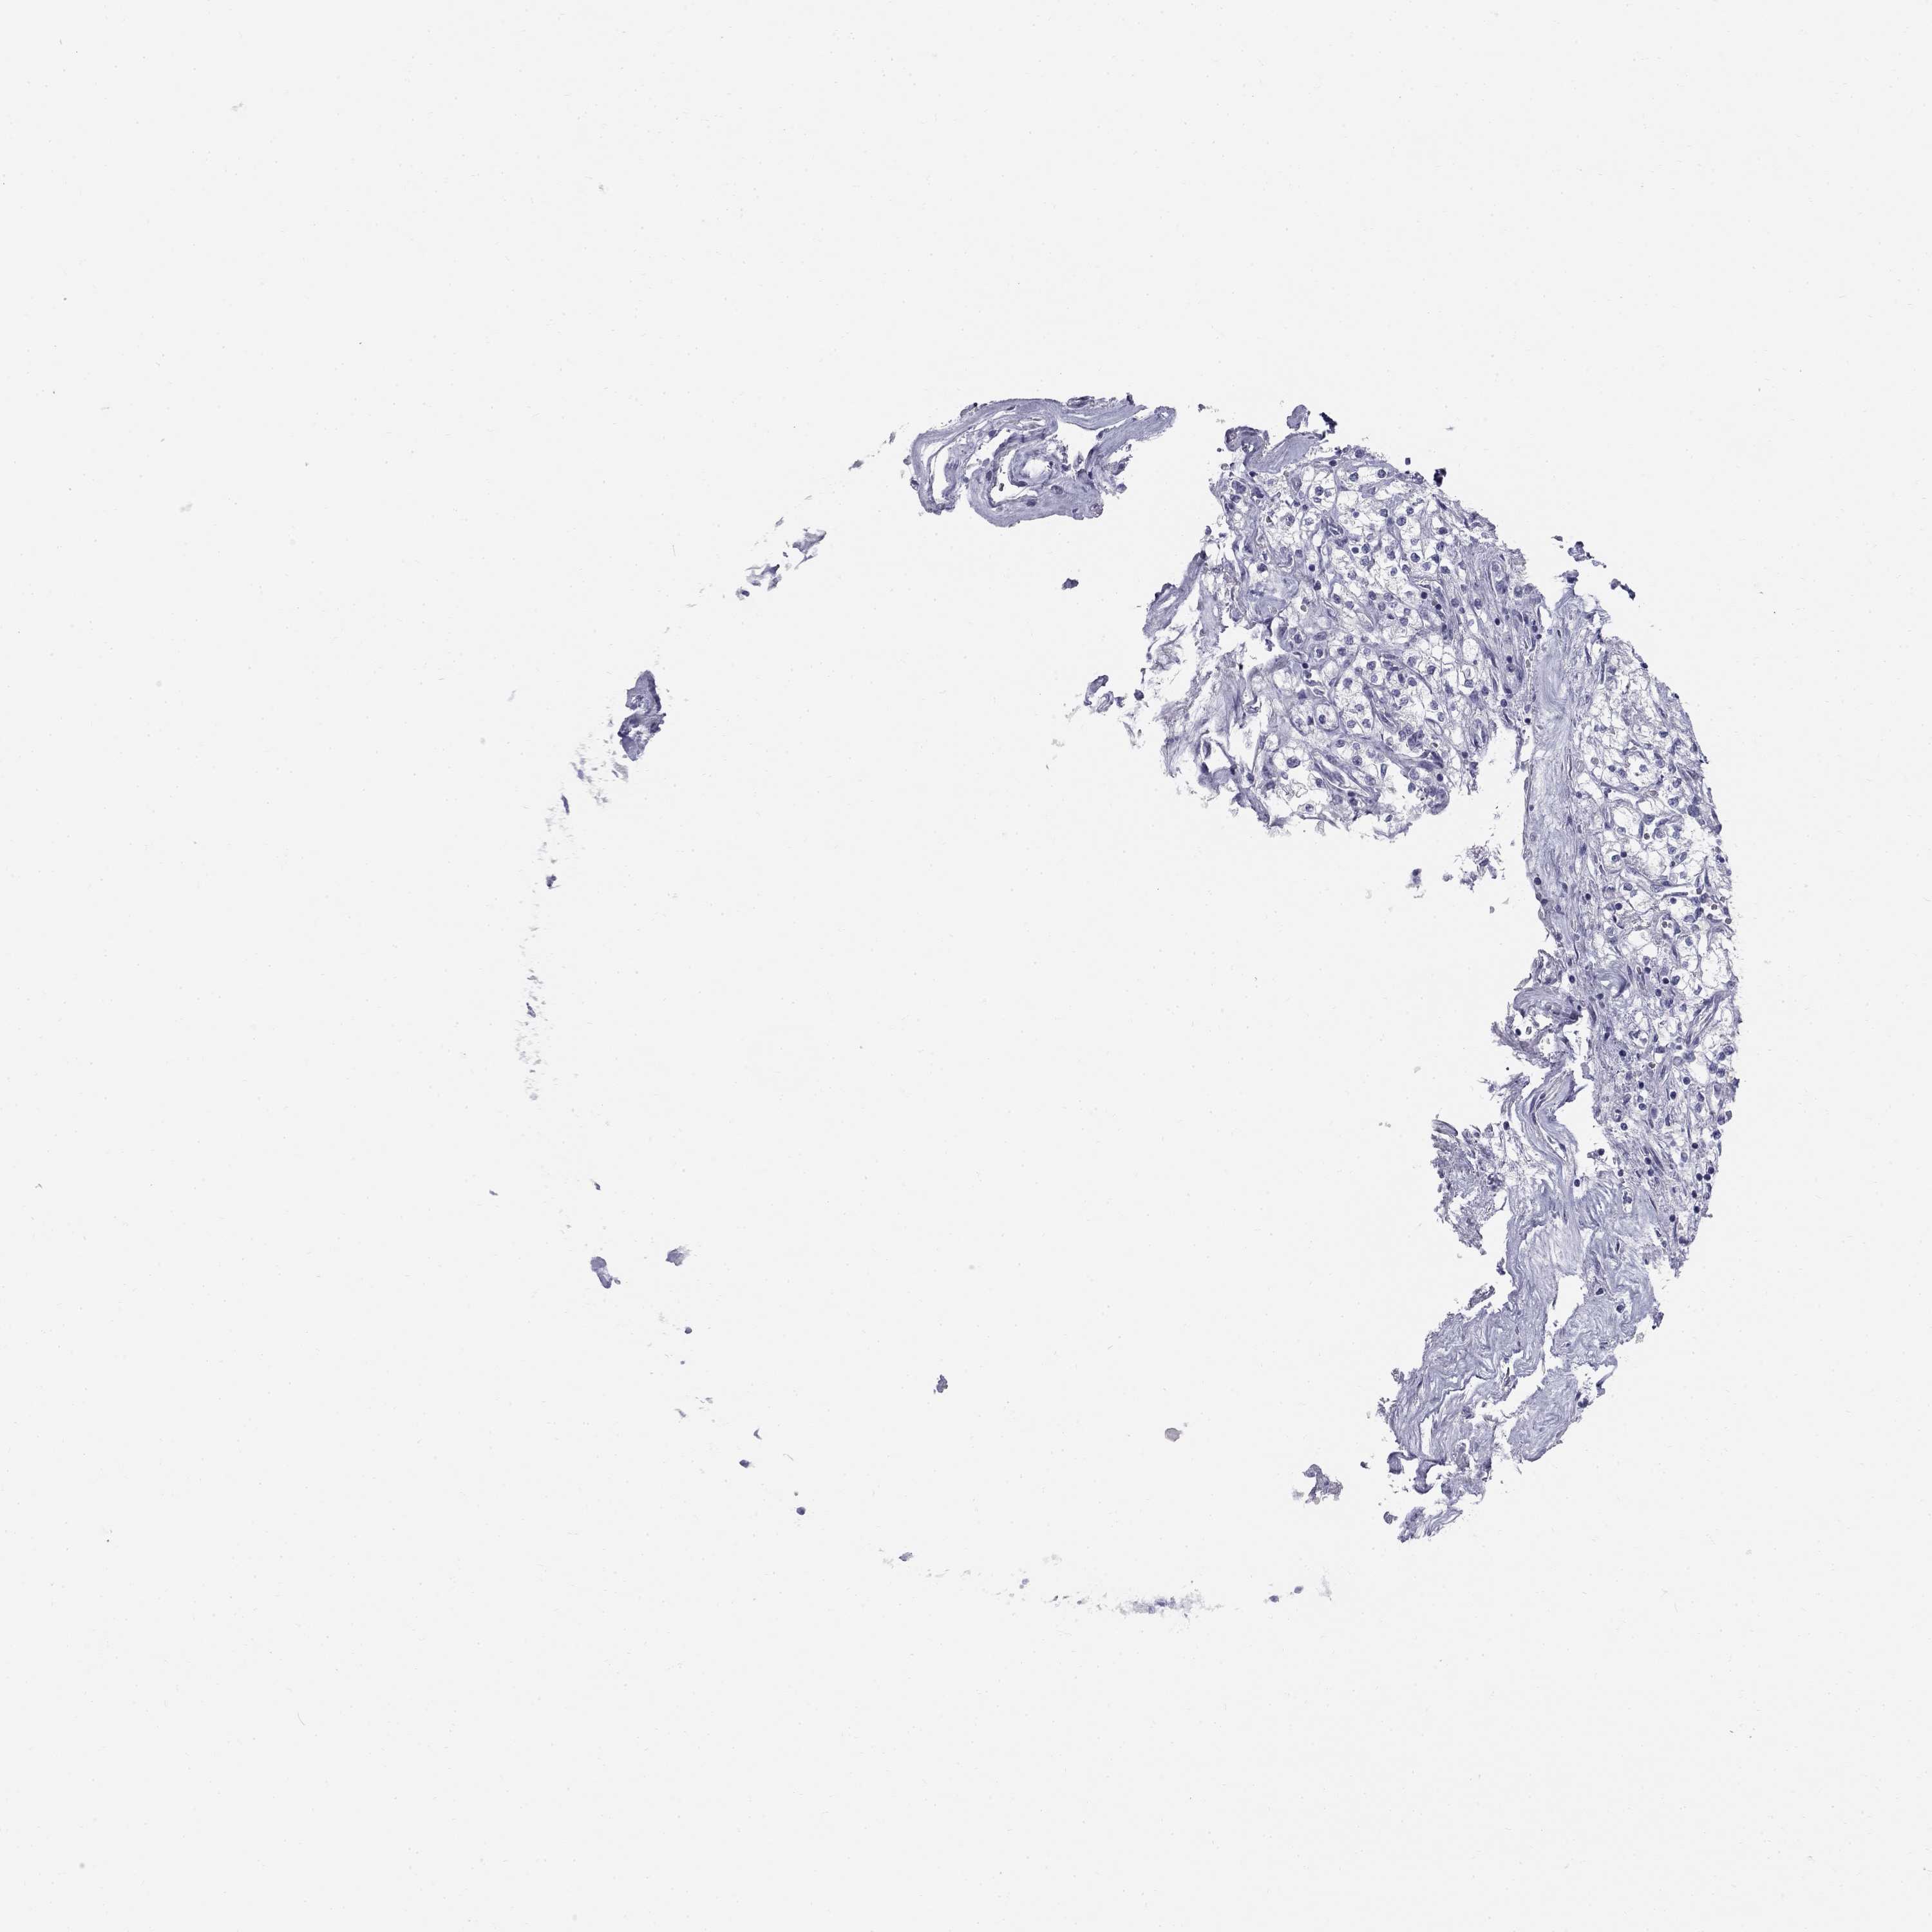

Average pTPM 1.2

Number of samples 100